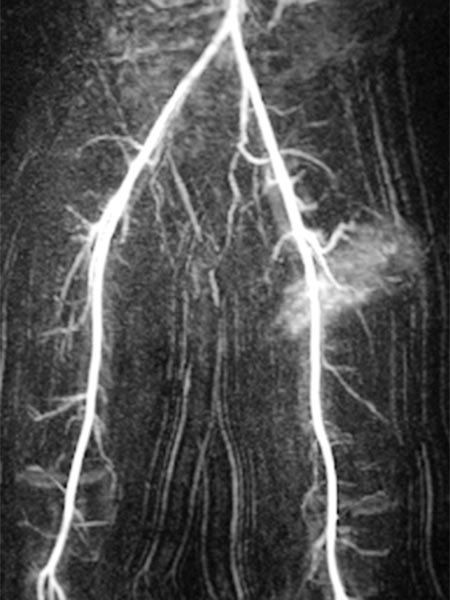

Kontrastmittelunterstützte, dynamische MR-Angiographie (koronare Schichtführung).

30 s nach KM-Injektion in der früharteriellen Phase kommt es zu einem sofortigen, frühen Enhancement des Tumors in der linken Leiste.

41 s nach KM-Injektion in der spätarteriellen Phase kommt es zu einem weiteren, eher diffusen, starken Enhancement des Tumors („tumor-blush“) in der linken Leiste, entsprechend einem soliden Gefäßtumor.

57 s nach KM-Injektion in der frühen venösen Phase reichert der gesamte Tumor weiterhin stark an. Es kontrastiert sich jetzt auch eine im Seitenvergleich stark erweiterte frühe Drainagevene. Durch die starke Tumorperfusion mit erhöhtem venösen Abstrom hat sich die venöse Drainage (Venae iliacae links) dilatiert.

130 s nach KM-Injektion in der späten Phase bleibt das starke Enhancement des Tumors in der linken Leiste erhalten, kein frühes „wash-out“. Auch die erweiterte venöse Drainage über die linken Iliakalvenen kontrastiert nach wie vor.